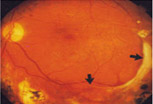

| Early Diabetic Retinopathy with Microhemorrhages |

NPDR, commonly known as background retinopathy, is an early stage of diabetic retinopathy. In this stage, tiny blood vessels within the retina leak blood or fluid. The leaking fluid causes the retina to swell or to form deposits called exudates. The beginning stages of diabetic retinopathy may cause blurriness in your central or peripheral (side) vision, or it may produce no visual symptoms at all. It mainly depends on where the blood vessel changes are taking place in your retina. Many people with diabetes have mild NPDR, which usually does not affect their vision.